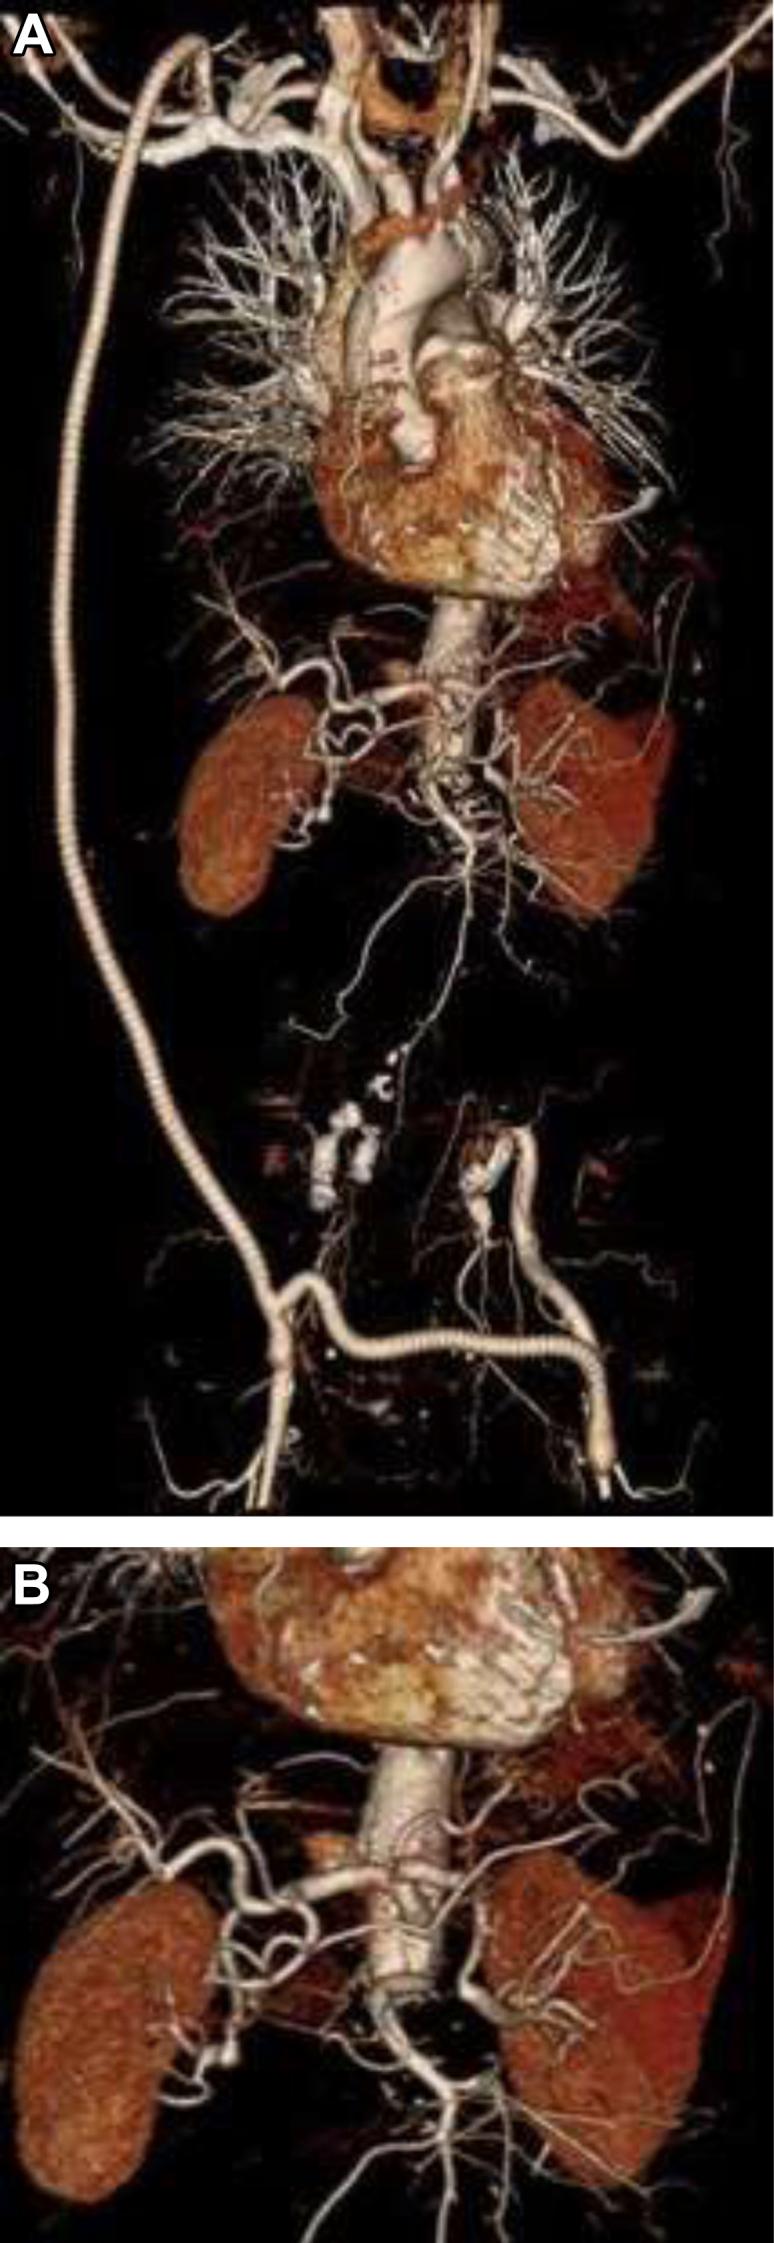

We report the case of an 82-year-old patient with an infected abdominal aortic endograft who presented with a right psoas abscess and lumbar osteomyelitis. The psoas abscess was drained percutaneously. Fluid obtained grew The patient, an active and highly functional individual, wished to pursue definitive management. The infected endograft was surgically removed, and the aorta was ligated above the renal arteries after staged axillary-bifemoral, hepatorenal, and splenorenal bypasses.

我们报告了一例82岁感染性腹主动脉内移植物患者,该患者出现右腰大肌脓肿和腰椎骨髓炎。经皮引流了腰大肌脓肿。引流获得的液体培养出……该患者积极且功能良好,希望进行确定性治疗。手术切除了感染的内移植物,并在分期进行腋-双股、肝-肾和脾-肾旁路手术后,在肾动脉上方结扎了主动脉。